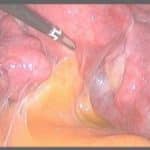

הלפרוסקופיה הינה כלי הבחירה באבחנה מדויקת של אנדומטריוזיס, מיקומה ודרגת חומרתה ומאפשרת טיפול כירורגי במחלה ללא פתיחת בטן.

ההחלטה על ביצוע לפרוסקופיה אינה פשוטה, ועליה להסתמך על גיל ותלונות המטופלת, הממצאים בבדיקה, הממצאים בהדמייה, תוכניות הפריון, טיפולי פריון קודמים ו/או ניתוחים קודמים

הלפרוסקופיה הינה כלי הבחירה באבחנה מדויקת של אנדומטריוזיס, מיקומה ודרגת חומרתה ומאפשרת טיפול כירורגי במחלה ללא פתיחת בטן. הלפרוסקופיה מאפשרת כריתת ציסטה שחלתית, הפרדת הידבקויות, כריתת נגעים לשם שיפור התלונות וטיפול באי הפריון. הלפרוסקופיה דורשת מיומנות ונסיון יחד עם עבודת צוות של מומחים בתחומים שונים לשם טיפול מיטבי